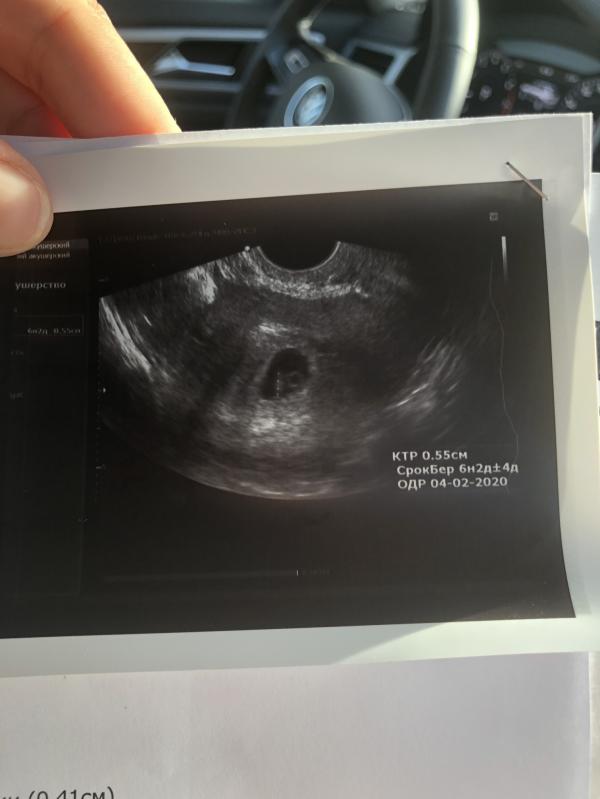

Самый счастливый день в нашей жизни🙏🏼🥰 услышав сердечко, не смогла сдержать слез☺️ Господи, как долго мы к этому шли, 3 года испытаний, стресса, неудач... и вот оно - СЧАСТЬЕ🙏🏼 малыш полностью соответствует сроку, от акушерского срока отличается ровно на неделю, но у меня длинный цикл, 34 дня, поэтому всё четко😉